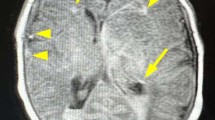

a, b Brain MRI of the patient’s mother (a, FLIAR image; b, T2* image). Note that the patient’s mother showed moderate brain atrophy. c, d Brain MRI of the patient’s sister (c FLAIR image; d T2* image). e, f MRI characteristics of the glioblastoma in the index patient (e FLAIR image; f gadolinium-enhanced T1-weighted image). g The resected brain tissue stained with hematoxylin and eosin. Note the marked hypercellularity, nuclear atypia, microvascular proliferation, and necrosis. Bar = 100 µm.

The epistaxis spontaneously subsided approximately 4 months after onset. Nine months after the onset of epilepsy, he developed weakness in his right upper and lower limbs. Brain MRI revealed a mass in the left frontal lobe, which was where FLAIR and DWI hyperintensity had been observed in the previous examination. The mass expanded aggressively and showed a ring-like enhancing pattern (Fig. 2e, f). The patient subsequently underwent resection followed by radiotherapy and temozolomide. Upon pathological examination of the resected tissue, a diagnosis of glioblastoma (WHO grade IV) was made. Genetic analysis of the specimen showed a mutation in the core promoter region of TERT (NC_000005.9(NM_198253.2):c.-146C>T) and wild-type IDH1 R132 and IDH2 R172, which is a typical pattern observed in grade IV glioblastoma13.